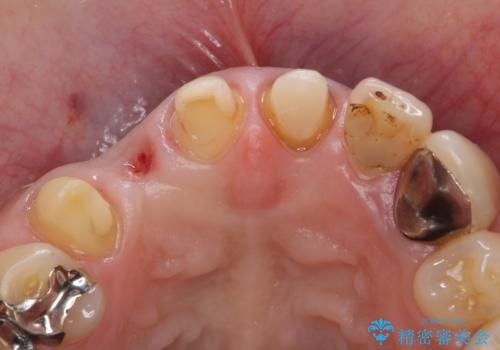

- 他院で治療したところ、右上2番目の歯の歯茎が下がってしまったので診て欲しいといらっしゃった方の症例です。

診査の結果右上2は歯根が破折しており、それが原因で骨及び歯肉の吸収が起きていました。

このまま右上2の抜歯を行うとさらに歯茎が下がる恐れがあったため、歯の挺出によって骨レベルを回復した上で抜歯し、歯槽堤保存術(抜歯窩に人工骨を填入する手術)を行いました。